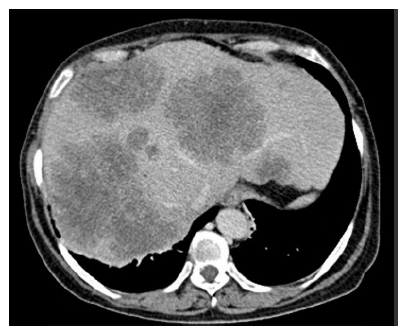

Paciente do sexo feminino, 62 anos de idade, relata dor abdominal em hipocôndrio direito há cerca de 1 mês e emagrecimento de 10 kg nos últimos 6 meses. Sem outras comorbidades. Nega história familiar de câncer de intestino. Ao exame físico: anictérica, palpada hepatomegalia dolorosa. A tomografia computadorizada de abdome evidenciou múltiplas metástases hepáticas inoperáveis e não passiveis de conversão. Tomografia computadorizada de tórax normal. CEA = 2.000 ng/ml. Colonoscopia mostrou lesão ulcerada em cólon sigmoide, ocupando 90% da luz do órgão. A biópsia da lesão em sigmoide confirmou adenocarcinoma de cólon. Pesquisa da mutação KRAS foi positiva.

Com base nesse caso clínico e nos conhecimentos médicos correlatos, julgue os itens a seguir.

Paciente do sexo feminino, 62 anos de idade, relata dor abdominal em hipocôndrio direito há cerca de 1 mês e emagrecimento de 10 kg nos últimos 6 meses. Sem outras comorbidades. Nega história familiar de câncer de intestino. Ao exame físico: anictérica, palpada hepatomegalia dolorosa. A tomografia computadorizada de abdome evidenciou múltiplas metástases hepáticas inoperáveis e não passiveis de conversão. Tomografia computadorizada de tórax normal. CEA = 2.000 ng/ml. Colonoscopia mostrou lesão ulcerada em cólon sigmoide, ocupando 90% da luz do órgão. A biópsia da lesão em sigmoide confirmou adenocarcinoma de cólon. Pesquisa da mutação KRAS foi positiva.

Com base nesse caso clínico e nos conhecimentos médicos correlatos, julgue os itens a seguir.

Paciente do sexo feminino, 62 anos de idade, relata dor abdominal em hipocôndrio direito há cerca de 1 mês e emagrecimento de 10 kg nos últimos 6 meses. Sem outras comorbidades. Nega história familiar de câncer de intestino. Ao exame físico: anictérica, palpada hepatomegalia dolorosa. A tomografia computadorizada de abdome evidenciou múltiplas metástases hepáticas inoperáveis e não passiveis de conversão. Tomografia computadorizada de tórax normal. CEA = 2.000 ng/ml. Colonoscopia mostrou lesão ulcerada em cólon sigmoide, ocupando 90% da luz do órgão. A biópsia da lesão em sigmoide confirmou adenocarcinoma de cólon. Pesquisa da mutação KRAS foi positiva.

Com base nesse caso clínico e nos conhecimentos médicos correlatos, julgue os itens a seguir.

Paciente do sexo feminino, 62 anos de idade, relata dor abdominal em hipocôndrio direito há cerca de 1 mês e emagrecimento de 10 kg nos últimos 6 meses. Sem outras comorbidades. Nega história familiar de câncer de intestino. Ao exame físico: anictérica, palpada hepatomegalia dolorosa. A tomografia computadorizada de abdome evidenciou múltiplas metástases hepáticas inoperáveis e não passiveis de conversão. Tomografia computadorizada de tórax normal. CEA = 2.000 ng/ml. Colonoscopia mostrou lesão ulcerada em cólon sigmoide, ocupando 90% da luz do órgão. A biópsia da lesão em sigmoide confirmou adenocarcinoma de cólon. Pesquisa da mutação KRAS foi positiva.

Com base nesse caso clínico e nos conhecimentos médicos correlatos, julgue os itens a seguir.

Paciente do sexo feminino, 62 anos de idade, relata dor abdominal em hipocôndrio direito há cerca de 1 mês e emagrecimento de 10 kg nos últimos 6 meses. Sem outras comorbidades. Nega história familiar de câncer de intestino. Ao exame físico: anictérica, palpada hepatomegalia dolorosa. A tomografia computadorizada de abdome evidenciou múltiplas metástases hepáticas inoperáveis e não passiveis de conversão. Tomografia computadorizada de tórax normal. CEA = 2.000 ng/ml. Colonoscopia mostrou lesão ulcerada em cólon sigmoide, ocupando 90% da luz do órgão. A biópsia da lesão em sigmoide confirmou adenocarcinoma de cólon. Pesquisa da mutação KRAS foi positiva.

Com base nesse caso clínico e nos conhecimentos médicos correlatos, julgue os itens a seguir.

Paciente do sexo feminino, 62 anos de idade, relata dor abdominal em hipocôndrio direito há cerca de 1 mês e emagrecimento de 10 kg nos últimos 6 meses. Sem outras comorbidades. Nega história familiar de câncer de intestino. Ao exame físico: anictérica, palpada hepatomegalia dolorosa. A tomografia computadorizada de abdome evidenciou múltiplas metástases hepáticas inoperáveis e não passiveis de conversão. Tomografia computadorizada de tórax normal. CEA = 2.000 ng/ml. Colonoscopia mostrou lesão ulcerada em cólon sigmoide, ocupando 90% da luz do órgão. A biópsia da lesão em sigmoide confirmou adenocarcinoma de cólon. Pesquisa da mutação KRAS foi positiva.

Com base nesse caso clínico e nos conhecimentos médicos correlatos, julgue os itens a seguir.